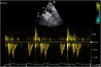

Uno de los cuadros clínicos más difíciles de manejar en el PC es la insuficiencia mitral que se produce por un movimiento anómalo de la valva anterior (SAM), generando un gradiente de presión en el TSVI o mesoventricular, arrastrando y succionando la valva anterior mitral (fig. 3). Debe sospecharse en casos con hipertrofia concéntrica, miectomía o implante de prótesis mitral con postes grandes que se dirigen hacia el TSVI, estados de hipovolemia y/o necesidad de soporte vasoactivo ascendente sin respuesta tensional apropiada.

PC de bypass coronario en paciente con hipertrofia del VI concéntrica: obstrucción dinámica TSVI por exceso de soporte inotrópico e hipovolemia postoperatoria, generando insuficiencia mitral severa por movimiento septal anterior (SAM). Obsérvese el flujo de aceleración progresiva por Doppler continuo.